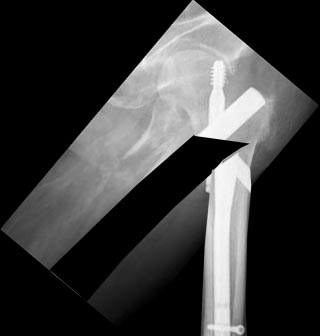

Пациент 63 года мужчина, остеосинтез чрезвертельного перелома проксимальным бедренным стержнем в октябре 2012. Постепенно появились и усилилиь боли в т.б.с., рентгенограммы показывают прорезание шеечного винта.

PDF, 131 Kb | Рентгенограммы до, после, через 2 мес и сейчас в приложении. Возможные варинаты: 1) реостеосинтез гамма-стержнем (но в наличии только 135-градусные, есть сомнения относительно фиксации винта в головке - вроде бы по первичным винт был установлен корректно, следовательно там сейчас полость); 2) реостеосинтез 95-клинковой пластиной. Просьба поделиться мнениями относительно возможных сложностей, за и против, может быть будут и другие варианты?